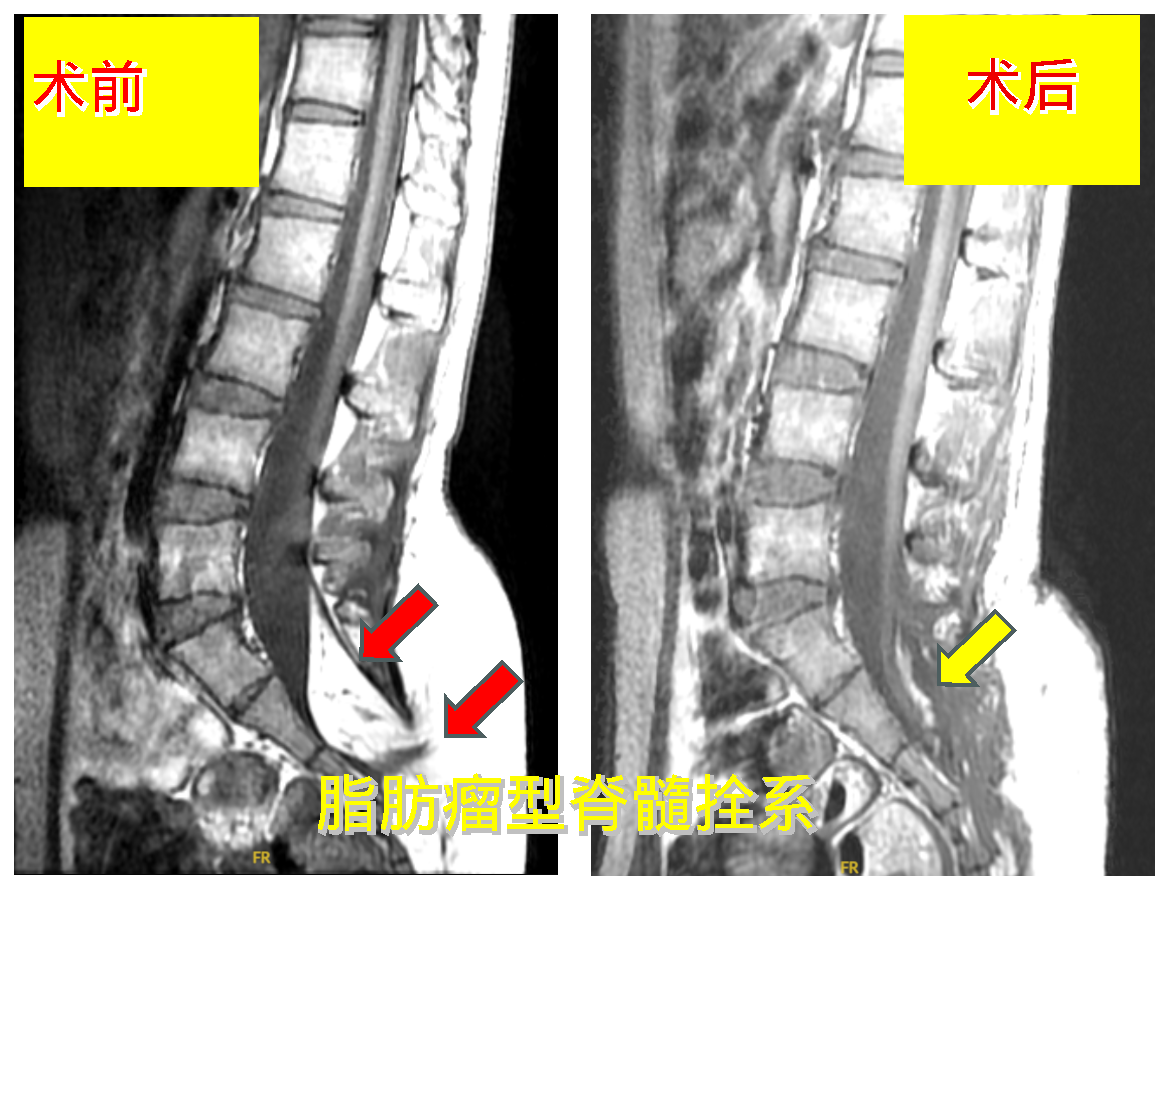

病例1.脂肪瘤型脊髓拴系,行脂肪瘤近全切除+拴系松解术